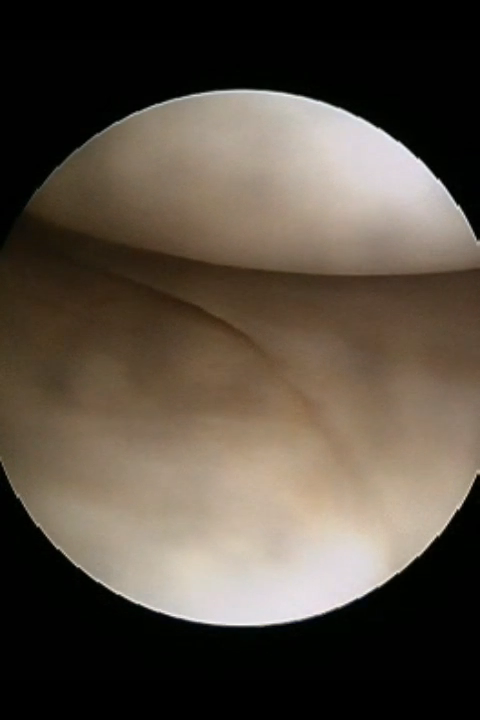

There used to be a common consensus that ACL reconstruction of knee should not be done in old age, this idea has now largely been debunked with statistical evidence. this 68 year old man with a traumatic anterior cruciate ligament tear had intact lateral and medial meniscus and quite normal cartilage in the weight bearing areas of knee, under such circumstances arthroscopic ACL repair should be done for a better outcome for the knee